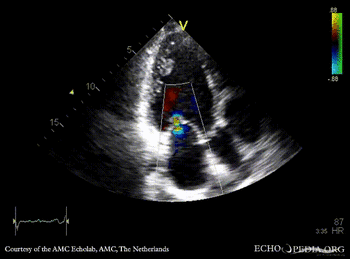

PLAX: dilated left ventricle, poor function, tenting of mitral valve PLAX with Color Doppler: severe mitral valve regurgitation